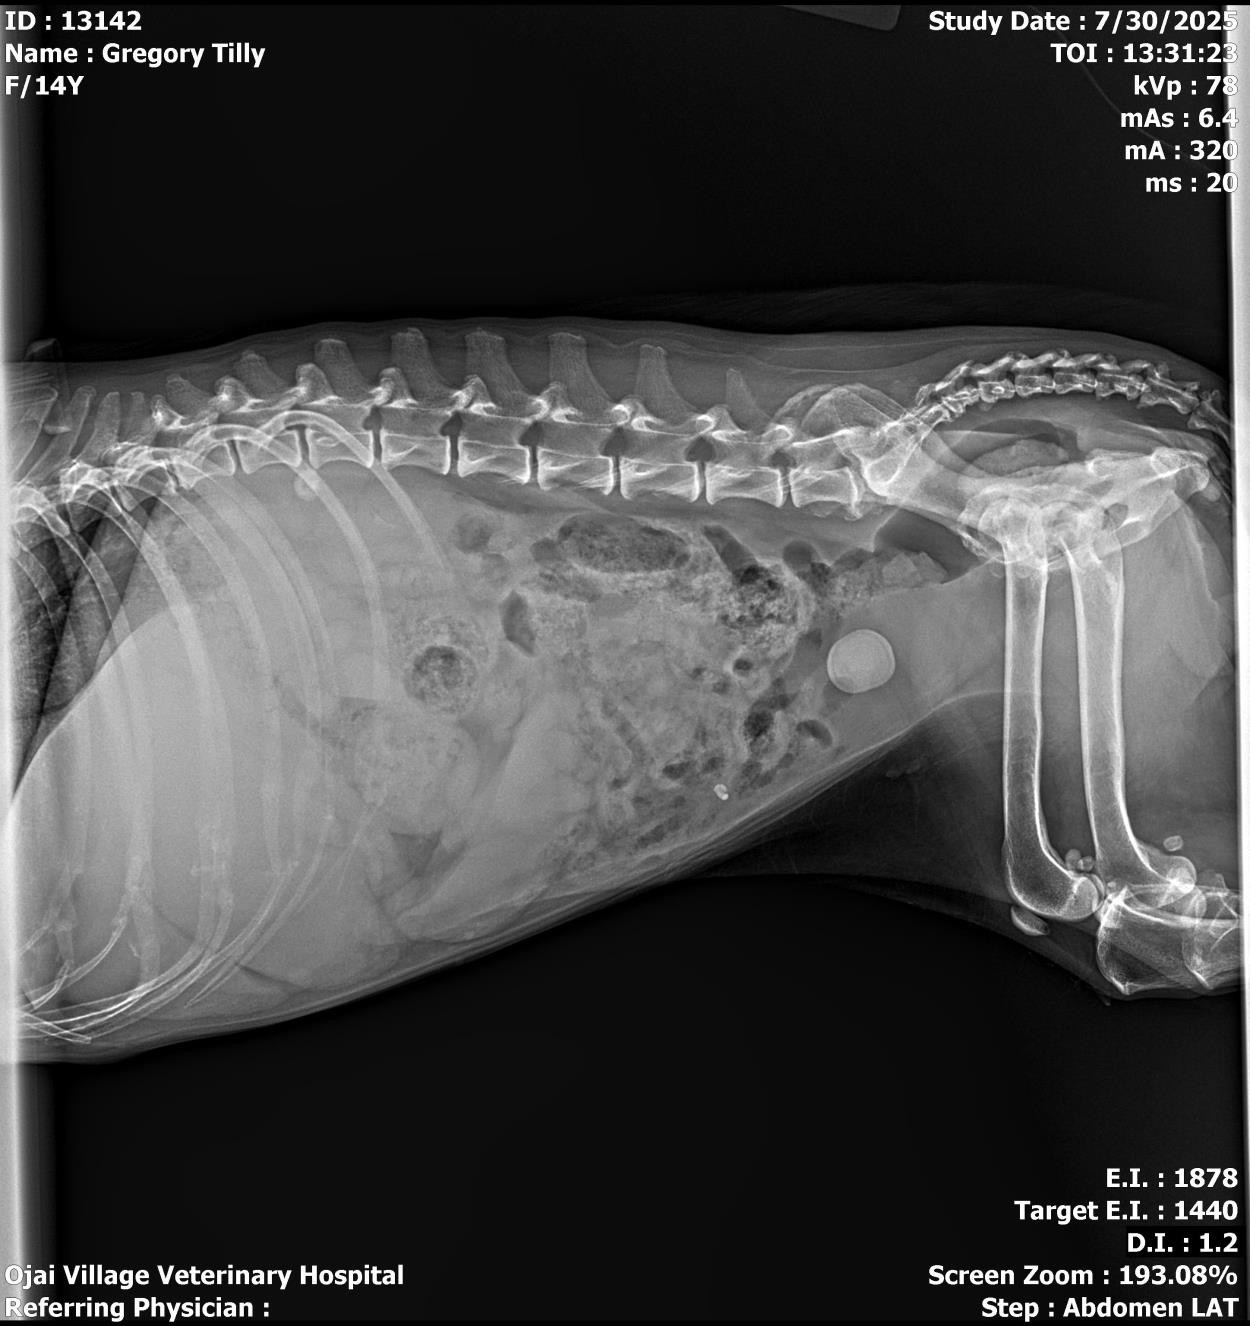

I adopted Tilly last Sept. when her long-time owner moved into assisted living and could no longer care for her. She is 13 years young and has a large bladder stone (app. 1”) that needs to be surgically removed before it causes a blockage. She is having a hard time urinating and pees blood as it painfully rubs against the inside of her bladder. She is a sweet old Beagle who only wants to love, , walk, nap, and hang with her cat, Kali. We just lost Bagel and finances are tight. Your LOVE and assistance are DEEPLY appreciated! Thank you! ♥️ A PHOTO OF THE LOW/HIGH ESTIMATE IS INCLUDED IN THE PHOTO GALLERY BELOW. <3